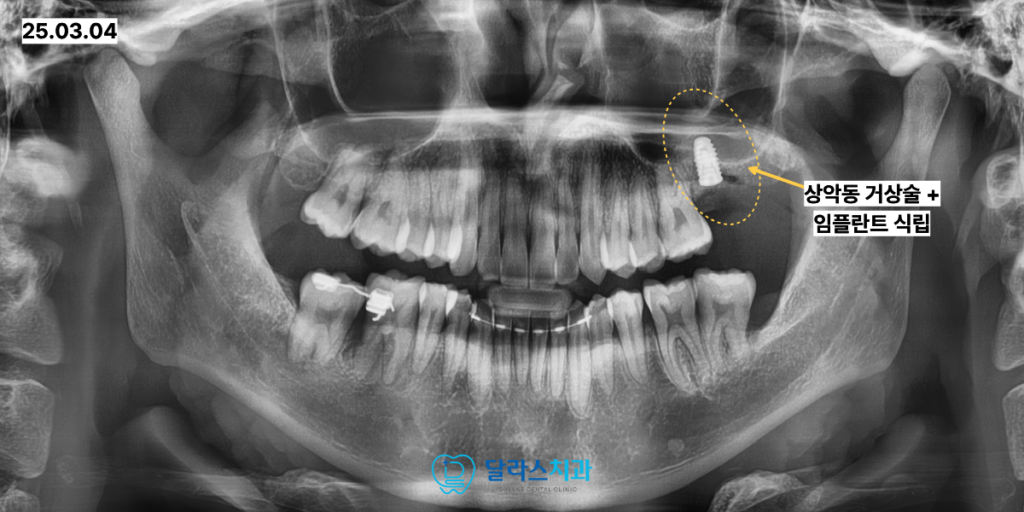

그 다음으로는 상악 좌측 큰어금니 역시 매복된 상태로 관찰되었습니다.

이 부위의 CT촬영을 동반한 정밀 분석 결과 치아를 아래로 견인하여 내려오게 하는 것이

현실적으로 매우 어렵고 성공률이 낮다는 판단이 내려졌습니다.

이에 따라 무리한 견인을 시도하기보다는 해당 치아를 발치한 후

부족한 뼈를 채워주는 골이식 술식을 병행하였습니다.

상악동 거상술을 함께 시행하여 임플란트가 식립될 충분한 공간을 확보하였고

최종적으로 임플란트를 식립하여 저작 기능을 회복해 드렸습니다.